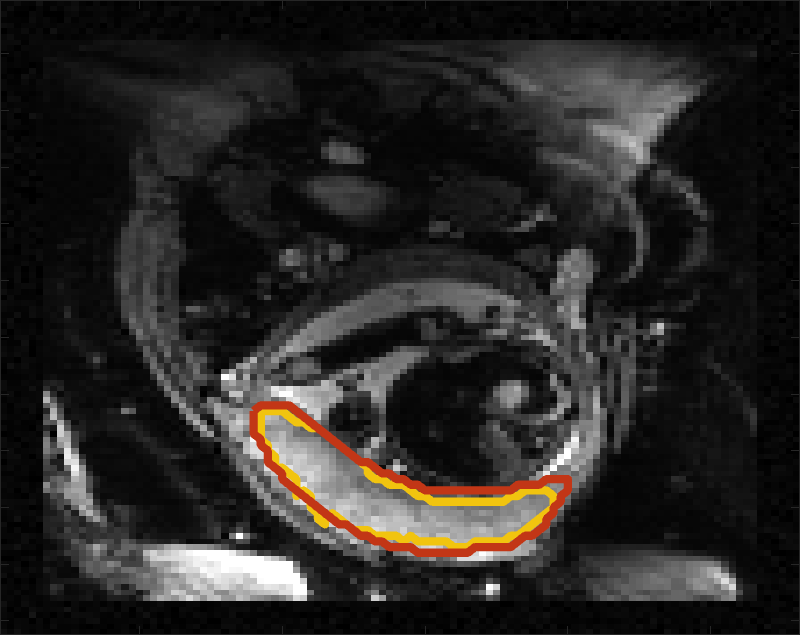

Despite its importance for many downstream clinical research tasks, placental segmentation is often performed manually and can take a significant amount of time, even for a trained expert. For BOLD MRI studies, manual segmentation is rendered more challenging due to the sheer number of MRI scans acquired and rapid signal changes due to the experimental design. Experiments acquire several hundred whole-uterus MRI scans to observe signal changes in three stages: i) normoxic (baseline), ii) hyperoxic, and iii) return to normoxic. During the hyperoxic stage, the BOLD signals increase rapidly, leading to hyperintensity throughout the placenta. Furthermore, the placental shape can undergo large deformation caused by maternal breathing, contractions, and fetal motion which can be particularly increased during hyperoxia [25]. See Fig. 1 for two examples.

Fig 3 compares the predicted label maps with ground truth on subjects with increasing Dice scores using the BW-CE model. The model accurately identifies the location of the placenta, but in the worst cases misses boundary details.